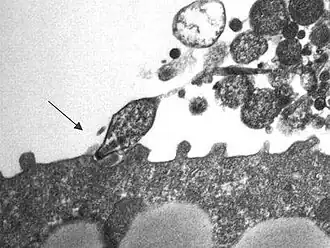

Mycoplasma pneumoniae (лат.) — вид бактерий рода Mycoplasma. Как и все бактерии этого рода, M. pneumoniae — мелкие микроорганизмы (0,3—0,8 мкм), не имеющие жёсткой клеточной стенки (в результате чего от внешней среды их отделяет лишь цитоплазматическая мембрана) и c ярко выраженным полиморфизмом. Строгий аэроб.